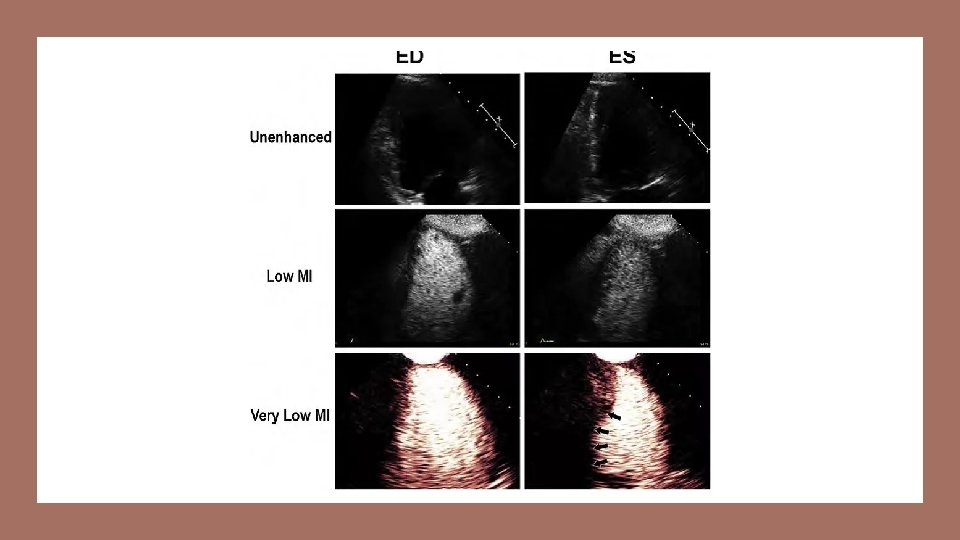

USE - Ultrasound New codes were established for ultrasound elastography, CPT 76981 -76983. These new codes distinguish reporting, per organ, first target lesion and each additional target lesion. Magnetic resonance elastography is new diagnostic imaging technology.

Cancer is harder than surrounding tissue

Microbubble Two new CPT codes 7697876979 are used to report ultrasound procedures that use dynamic microbubblesonographic contrast with targeted ultrasound to evaluation lesions.